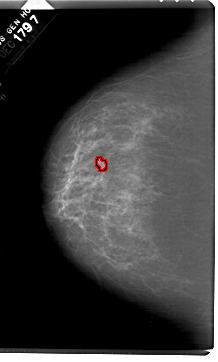

A_1518_1.RIGHT_CC

RIGHT_CC LINES 6871 PIXELS_PER_LINE 4066 BITS_PER_PIXEL 12 RESOLUTION 43.5 NON_OVERLAY

FILE: A_1518_1.LEFT_CC.OVERLAY

TOTAL_ABNORMALITIES 1

ABNORMALITY 1

LESION_TYPE MASS SHAPE LOBULATED MARGINS ILL_DEFINED

ASSESSMENT 4

SUBTLETY 2

PATHOLOGY BENIGN

TOTAL_OUTLINES 1

BOUNDARY